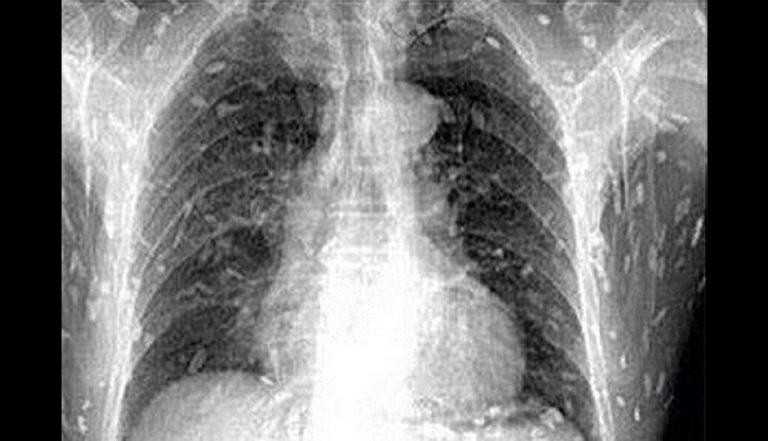

Ele relatou que esses sintomas já estavam acontecendo há uma semana. Depois de realizarem uma endoscopia, os médicos descobriram que havia larvas do gênero Anisakis dentro do estômago dele.

Tal condição é causada quando se ingerem peixes e frutos do mar crus ou malcozidos contaminados com larvas desse parasita, de acordo com o Centro de Controle e Prevenção de Doenças dos Estados Unidos (CDC).

As coisas foram esclarecidas quando o paciente revelou que tinha comido sushi recentemente. Caso as larvas que estavam em seu corpo atingissem seu cérebro, o homem poderia ter morrido, mas isso não aconteceu pois ele foi ao hospital rapidamente, o que foi importante para sua recuperação.